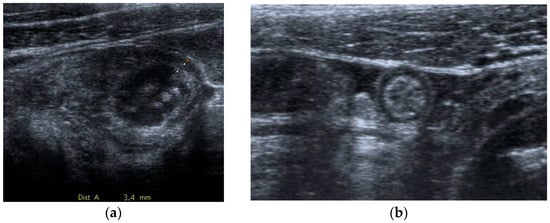

Figure 7.

Acute pyelonefritis in a 28-year-old woman at 23 weeks of gestation presenting with right-sided abdominal pain and fever. Axial T2WI fat-sat image (a) shows an enlarged right kidney with a dilated pelvis. Axial DWI b-800 (b) clearly depicts wedge-shaped areas of high signal intensity in the right kidney, consistent with the foci of nephritis.

In patients who develop renal abscesses, T2-weighted and DW images respectively show a focal, more hyperintense signal and restricted diffusion, compared to the rest of the parenchyma involved in nephritis [3,54] (Figure 8).

Figure 8.

A 21-year-old woman at 20 weeks of gestation was admitted to the hospital with a diagnosis of pyelonephritis and a temperature of 39.4 °C. Coronal T2-weighted HASTE (a) and axial T2-weighted fat-sat images (b) show a large right-sided and thick-walled fluid collection (arrows), consistent with renal abscess, displacing the kidney.